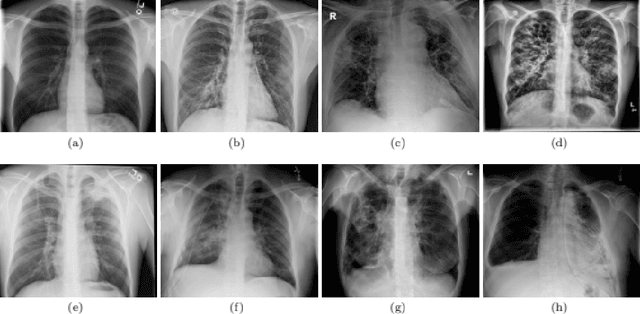

Abstract:The world is going through a challenging phase due to the disastrous effect caused by the COVID-19 pandemic on the healthcare system and the economy. The rate of spreading, post-COVID-19 symptoms, and the occurrence of new strands of COVID-19 have put the healthcare systems in disruption across the globe. Due to this, the task of accurately screening COVID-19 cases has become of utmost priority. Since the virus infects the respiratory system, Chest X-Ray is an imaging modality that is adopted extensively for the initial screening. We have performed a comprehensive study that uses CXR images to identify COVID-19 cases and realized the necessity of having a more generalizable model. We utilize MobileNetV2 architecture as the feature extractor and integrate it into Capsule Networks to construct a fully automated and lightweight model termed as MobileCaps. MobileCaps is trained and evaluated on the publicly available dataset with the model ensembling and Bayesian optimization strategies to efficiently classify CXR images of patients with COVID-19 from non-COVID-19 pneumonia and healthy cases. The proposed model is further evaluated on two additional RT-PCR confirmed datasets to demonstrate the generalizability. We also introduce MobileCaps-S and leverage it for performing severity assessment of CXR images of COVID-19 based on the Radiographic Assessment of Lung Edema (RALE) scoring technique. Our classification model achieved an overall recall of 91.60, 94.60, 92.20, and a precision of 98.50, 88.21, 92.62 for COVID-19, non-COVID-19 pneumonia, and healthy cases, respectively. Further, the severity assessment model attained an R$^2$ coefficient of 70.51. Owing to the fact that the proposed models have fewer trainable parameters than the state-of-the-art models reported in the literature, we believe our models will go a long way in aiding healthcare systems in the battle against the pandemic.